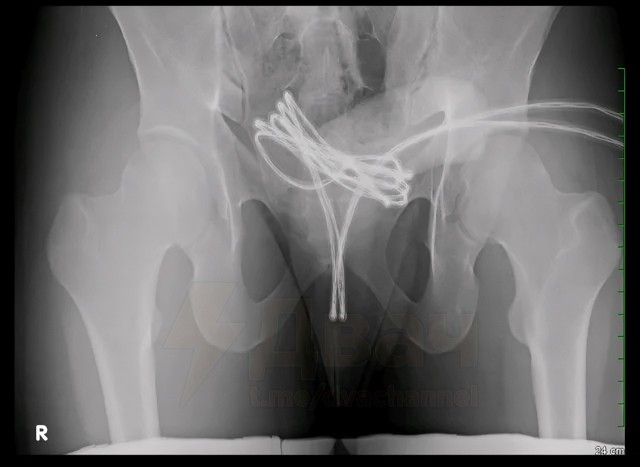

Сверхразум рассказал, что раньше уже вставлял себе в пенис ватные палочки и провода, но в этот раз переборщил: свернул кабель в петлю, оставил концы снаружи, но потом не смог достать.

Кабель дошёл до мочевого пузыря. Врачи вытащили его только под наркозом. Парень провёл неделю в больнице — ему кололи обезболивающее и антибиотики.

Такой фетиш называется саундинг — когда в уретру вводят разные предметы ради возбуждения. Люди используют, например, иголки, батарейки или даже скакалки. Это опасно: можно пораниться или занести инфекцию.

21-летний американец засунул себе в уретру USB-кабель